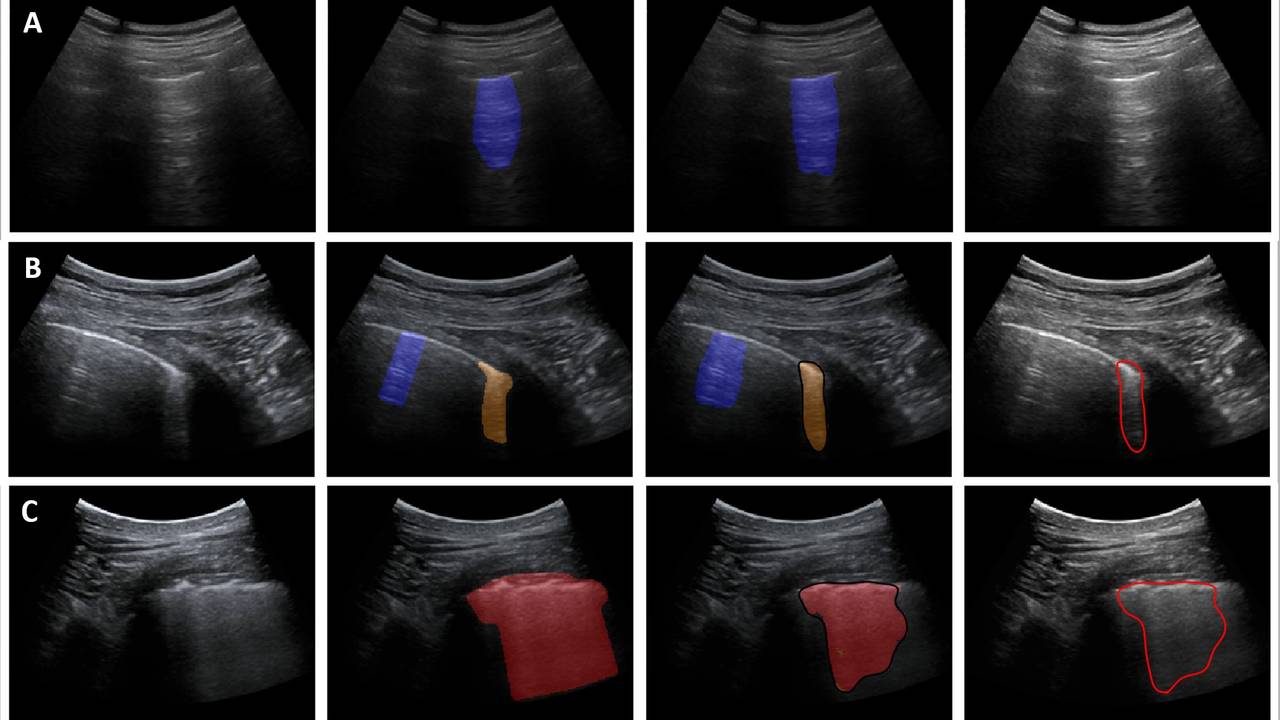

De techniek kan besmetting met het coronavirus niet onomstotelijk bewijzen, maar een longecho kan wel afwijkingen aan het licht brengen die daarop wijzen. De beelden worden automatisch geanalyseerd door het computerprogramma.